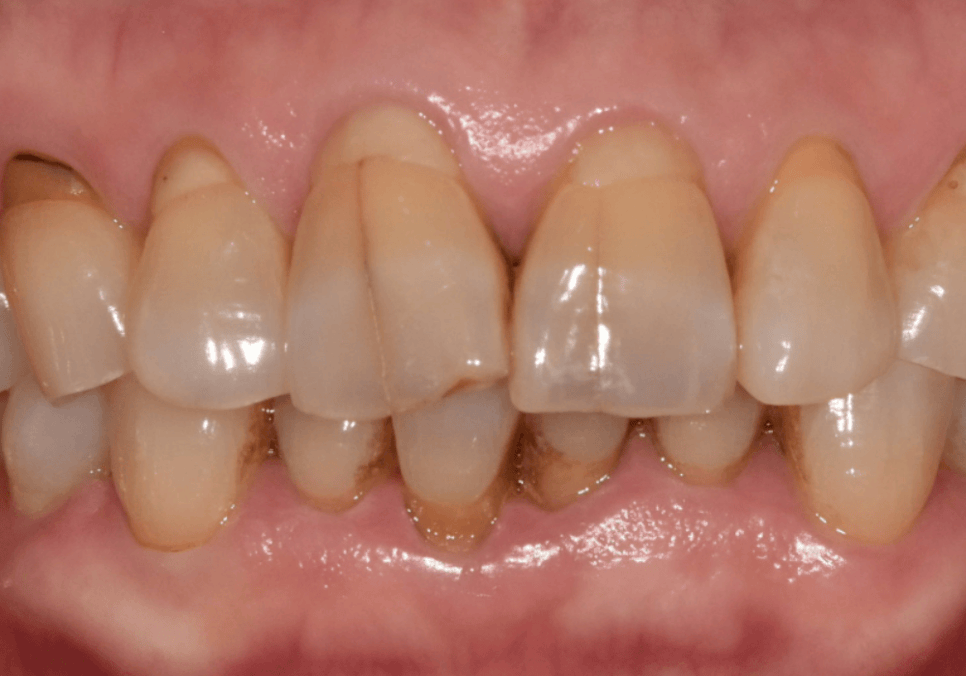

최근 저희 치과에 내원하신

한 남성분도 비슷한 경우였습니다.

평소 얼음을 치아로 깨 먹는 걸 즐기실 정도로

딱딱한 식감을 유독 좋아하셨다고 해요.

그러다 얼마 전

갈비를 앞니로 뜯는 순간,

대문니인 앞니 두 개에 금이 쩍!하고 가서

놀란 마음으로 방문하셨습니다.

입안을 직접 살펴보니

굳이 말씀을 안 하셔도...

평소 식습관을 알 수 있을 정도였는데요~

치아의 씹는 면이

맷돌처럼 평평하게 마모되어 있었고

군데군데 작게 깨진 흔적들도 많았거든요.

특히 치아와 잇몸이 만나는 목 부위가

도끼로 찍은 듯 파여있는

치경부 마모 증상도 관찰되었습니다.

251229

강한 힘으로 음식을 씹을 때

치아가 미세하게 휘어지면서

가장 약한 목 부분이 떨어져 나가는 현상이죠.

이는 딱딱한 음식을 즐기는 분들에게

흔히 나타나는 징후들입니다.